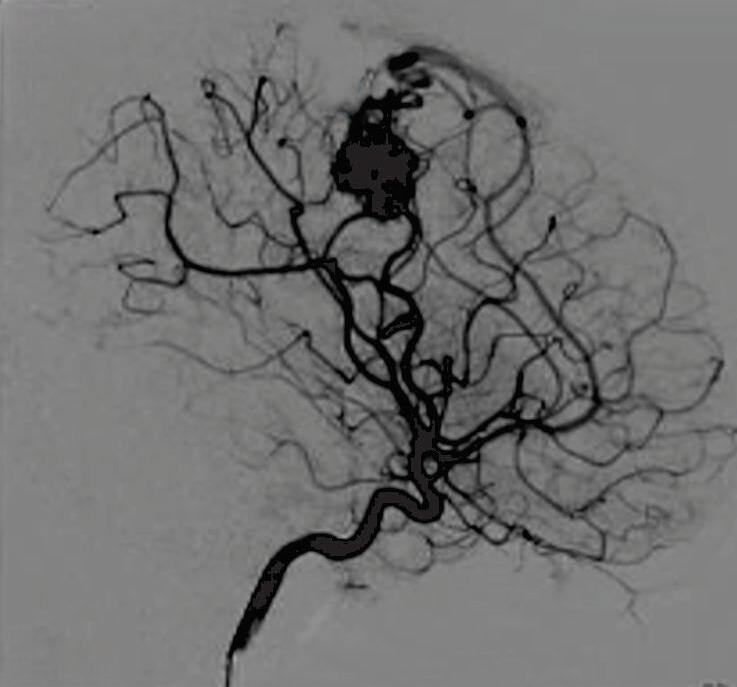

Com relação ao fluxo no interior do nidus, alguns autores classificam-nas em alto fluxo (Fig. 1-8) e baixo fluxo (Fig. 1-9). São consideradas de alto fluxo aquelas em que a opacificação após injeção de contraste ocorre apenas na malformação, em contrapartida, nas de baixo fluxo, ocorre opacificação da MAV e de outras artérias normais do mesmo território vascular. Exemplificando as lesões de alto fluxo temos as malformações arteriais, as malformações arteriovenosas e as fístulas arteriovenosas, enquanto as lesões de baixo fluxo são representadas pelas malformações venosas, linfáticas e capilares.25

Fig. 1-9. RNM T2 em cortes (a) axial e (b) sagital. (c,d) Tractografia axial – sagital, demonstrando a posição de uma MAV não rota localizada na superfície basal do lobo frontal, nos giros orbitários e reto à direita (setas longas). Arteriografia digital cerebral com injeção de contraste via carótida direita, (e) AP e (f) em perfil demonstrando MAV nutrida por ramos da artéria cerebral média e cerebral anterior direita e drenagem para o seio sagital superior (seta curta).